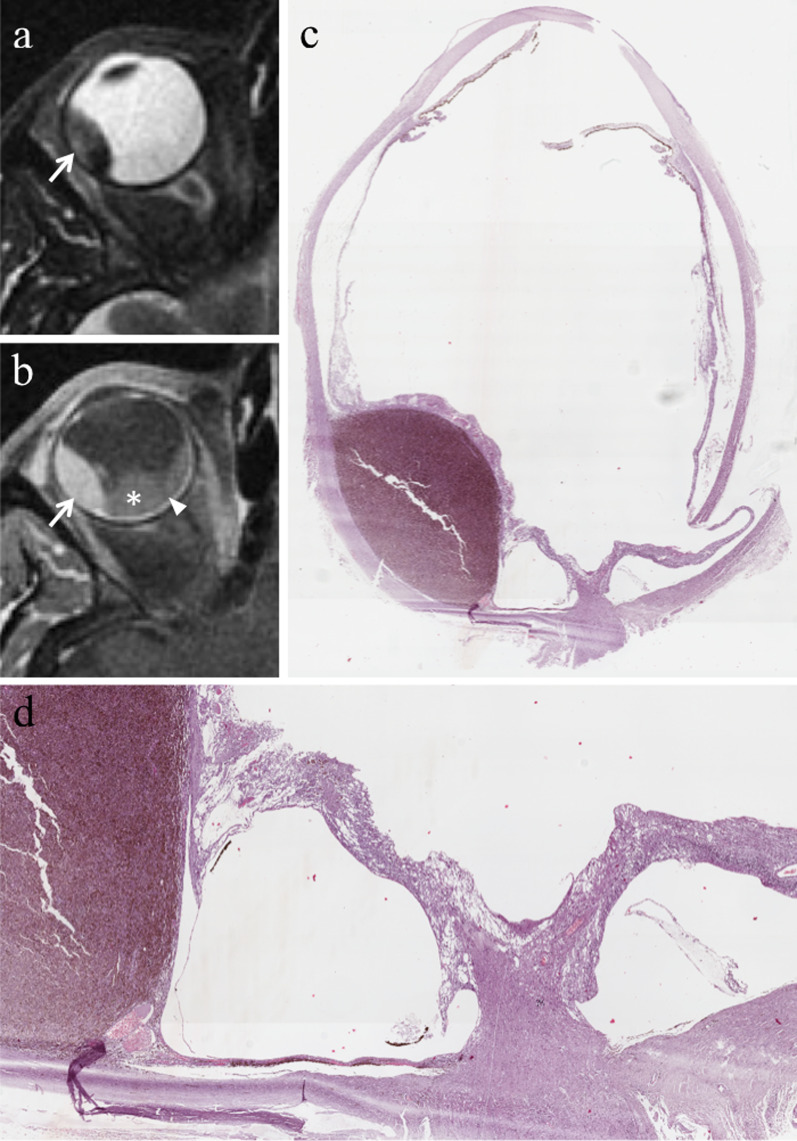

At MRI, regardless of its content, a localized choroidal detachment appears as a focal, well defined, smooth, lentiform or, dome- or mound shaped mass. Serous choroidal detachment is hypointense on T1-weighted images and hyperintense on T2-weighted images (Fig. 18). On the other hand, the signal intensity of hemorrhagic choroidal detachment varies based on its age. In the first two days the hematoma appears slightly hypointense-isointense with the vitreous body on T1-weighted sequences and hypointense on T2-weighted sequences. Later, hemorrhagic choroidal detachment is hyperintense on T1-weighted and hypointense on T2-weighted images. Chronic hemorrhagic choroidal detachment (age ≥ 3 weeks) usually appears hyperintense on both T1- and T2-weighted sequences.

Fig. 18.

A 70-year-old man with serous choroidal detachment and hemorrhagic retinal detachment due to a large lobulated pigmented choroidal melanoma along the medial and inferior aspect of the right eye. Axial (a) T2-weighted turbo spin-echo STIR and (b) fat-suppressed T1-weighted images, (c) coronal and (d) axial contrast-enhanced fat-suppressed T1-weighted images. The intraocular mass along the medial and inferior aspect of the globe exhibits low signal intensity on T2-weighted image (white arrow in a), high signal intensity on T1-weighted image (white arrow in b) and mild enhancement after contrast agent administration (white arrows in c and d). Along the supero-lateral aspect of the eyeball, the localized serous choroidal detachment, with its well-defined lentiform shape, is hyperintense on T2-weighted (black asterisk in a) and hypointense on T1-weighted images (white asterisk in b); the detached choroid is easily appreciable after contrast agent administration (white arrowheads in c and d) because of its enhancement. The coexisting hemorrhagic retinal detachment demonstrates low signal intensity on T2-weighted image (white dotted arrow in a), high signal intensity on T1-weighted image (white dotted arrow in b) and does not enhance after contrast agent administration (white dotted arrow in d). The lens is displaced anteriorly (white curved arrow in a). e Histological examination: low magnification showing a pigmented uveal melanoma (below) and the coexisting choroidal detachment (on the left) (H&E, original magnification ×25)

Retinal and choroidal detachments may have a quite similar appearance; however, some tips and tricks may allow to differentiate them. The leaves of the retinal detachment posteriorly stretch up to the site of the optic disk and anteriorly reach the ora serrata; on the other hand, the leafs of the choroidal detachment posteriorly do not reach the optic disk and anteriorly may involve the ciliary body, thus resulting in a ciliary detachment. Furthermore, the inner boundary of the choroidal detachment is constituted by the choroid and retina together, therefore enhances after i.v. administration of paramagnetic contrast agent and is thicker than that of the retinal detachment, represented by the retina alone (Table 4). Lastly, it should be remembered that, unlike retinal detachment which often accompanies uveal melanoma, choroidal detachment is very rarely associated with uveal melanoma. [23].